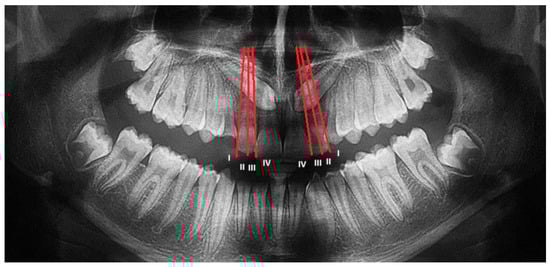

The Lindauer [2] sector division was considered to evaluate the mesio-distal position of canines’ cusps. The authors described four sectors, listed in order of severity of prognosis:

Sector I: area distal to the line tangent to the distal surface of the lateral incisor;

Sector II: area mesial to sector I, distal to the line that divides the mesiodistal surface of the lateral incisor along its major axis;

Sector III: area mesial to sector II, distal to the line tangent to the mesial surface of the lateral incisor;

Sector IV: includes the area mesial to Sector III (Figure 2).

Sector of inclusion measured on OPT according to Lindauer. Both maxillary canines are included in sector IV.